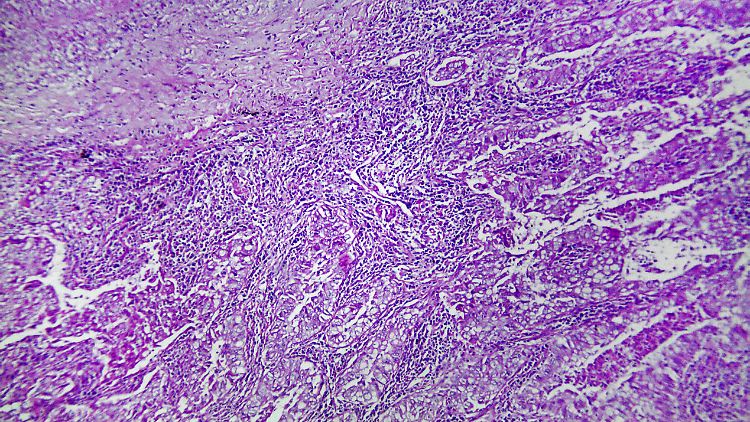

Der neue Bluttest erkannte bei 100 Prozent der Patienten mit Lungenkarzinom im fortgeschrittenen Stadium Tumor-Erbgut im Blut.

(Foto: imago stock&people)

Beim nicht-kleinzelligen Lungenkarzinom (NSCLC), der häufigsten Form von Lungenkrebs, erkannte das kostengünstige Verfahren Tumor-Erbgut im Blut aller Patienten im fortgeschrittenen Stadium und bei jedem Zweiten im Frühstadium. Das berichten Mediziner um Maximilian Diehn von der US-amerikanischen Stanford University im Fachblatt "Nature Medicine".

In Tests spürte das Verfahren Tumor-DNA bei 100 Prozent der NSCLC-Patienten ab Stadium II und bei 50 Prozent der Patienten im Stadium I auf. Das Verfahren hatte nicht nur eine hohe Trefferquote, sondern lieferte auch kaum irrtümliche Krebsbefunde. Darüber hinaus gab die Menge der ctDNA Aufschluss über die Größe des Tumors und auch über seine Entwicklung während der Therapie - teilweise sogar besser als Biopsien.